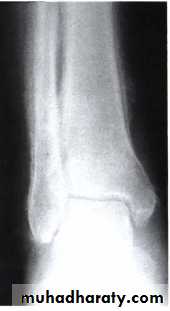

LUNG CANCER - Dr. Mustafa Nema- Baghdad College of MedicineClubbing

Hypertrophic pulmonary osteoarthropathy (HPO)Characterized by periostitis of the long bones, most commonly the distal tibia, fibula, radius and ulna.

This gives rise to pain and tenderness over the affected bones and often pitting oedema over the anterior aspect of the shin.

X-rays of the painful bones show subperiosteal new bone formation.

Clubbing is part of HPO.